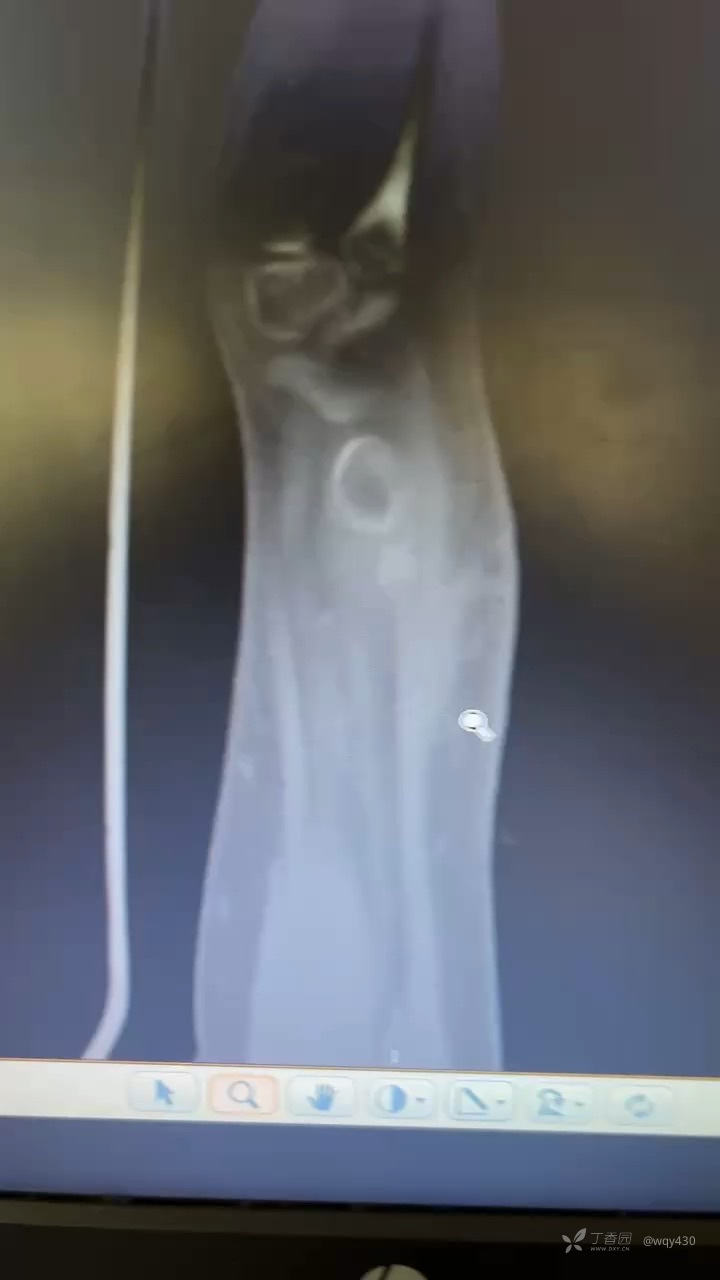

下面是术后约10

求下一步治疗方案1再次内固定,钢板or克氏针

2外固定架3先姑息观察,进一步再手术